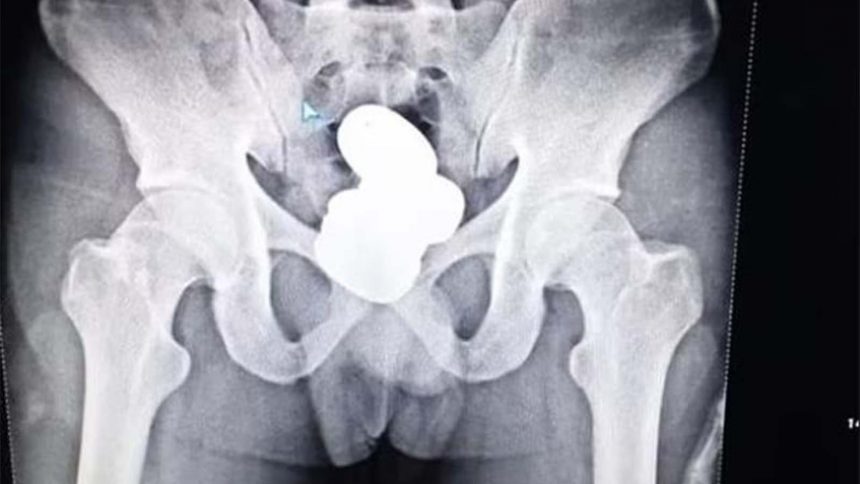

Безбедносната проверка пред поаѓање открила присуство на метал во неговото тело. По првичното испрашување, Шериф, од Кожикоде во јужната област Керала, бил однесен во просторијата за медицински преглед за да направи рендген снимка, која открила дека тој крие „метални предмети во телесна празнина“.

Рендген снимките покажале големи грутки златна паста во ректумот на Шериф, иако патникот им рекол на полицајците дека само го носи златото и дека не го поседува.